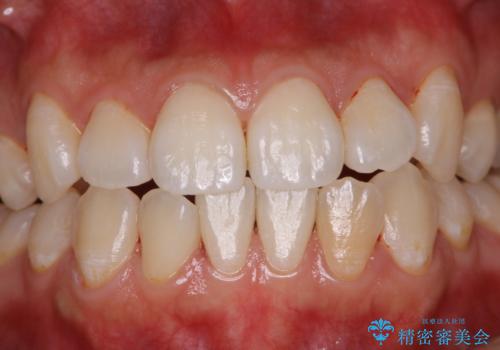

1日で着色を除去し綺麗な歯に

- 前歯の汚れが気になるため、綺麗にしたいとのことで来院されました。PMTC30分コースを行いました。

毎日丁寧に歯磨きをしていても、日常生活での飲食物などにより着色してしまうことはあります。PMTCでは、歯の表面の凸凹にミネラルを補給して、ツルツルの表面に仕上げます。定期的にPMTCを行うことにより、歯質の強化になり着色がつきにくい状態になります。